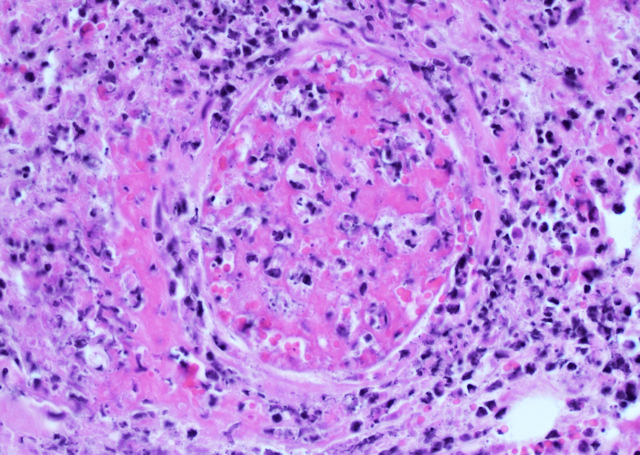

Infarkte entstehen infolge einer Durchblutungsstörung. Und tatsächlich wiesen die Blutgefäße in der Umgebung Nekrosen auf bzw. waren durch Thromben verlegt, ebenfalls mit zahlreichen Schimmelpilzhyphen (Bild 6).

Bild 6: Fibrinoide Gefäßnekrose, HE-Färbung, 400fache Vergrößerung

Die Hyphen stellten sich als relativ breit (5-20 µm), wenig septiert, mit rechtwinkligen, 45° und dichotomen Verzweigungen dar und waren stark fragmentiert. Eine sichere Unterscheidung zwischen Mucorales und Aspergillus spp. war mittels feingeweblicher Untersuchung nicht möglich. Aufgrund der wenig bis nicht septierten Hyphen und der Affinität zu Blutgefäßen mit Thrombusbildung wurde der Verdacht auf eine Infektion mit Mucorales erhoben.

Die Pilze können in die Blutgefäße eindringen und, wie in diesem Fall, Thrombosen und Infarkte verursachen. Daher kommt es häufig zu Nekrosen, die alle Schichten der Vormagenwand betreffen. Außerdem können sie über das Blutgefäßsystem in andere Organe wie die Leber abgeschwemmt werden und dort ebenfalls Entzündungen hervorrufen.